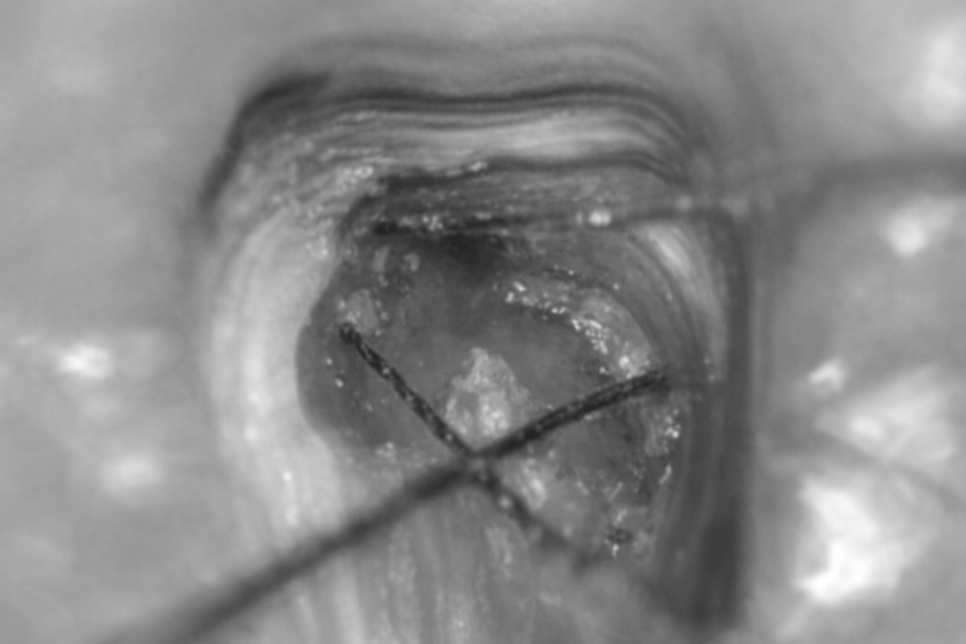

연세대학병원에서 사용하고 있는 모델인

Carl Zeiss 미세 현미경을 기준으로

설명해 드리겠습니다

약 25배까지 확대된 시야를 얻을 수 있어

구조적 한계나 협착되어 발견조차 어려울 때,

활용하면 더 넓은 시야를 확보할 수 있어

입구를 찾아 소독하는 과정이 수월해집니다.

25배 확대된 시야로 봐도

치아 내부 구조가 매우 좁고 작죠?!ㅎㅎ

맨눈으로 봤을 때는 한계가 더욱 많기에

그 한계를 넘어서는데 확실히 도움이 됩니다.

당산동 치과 예시 사진처럼

MB2와 DL root를 찾아 NITI-File이

수월하게 진입할 수 있죠.